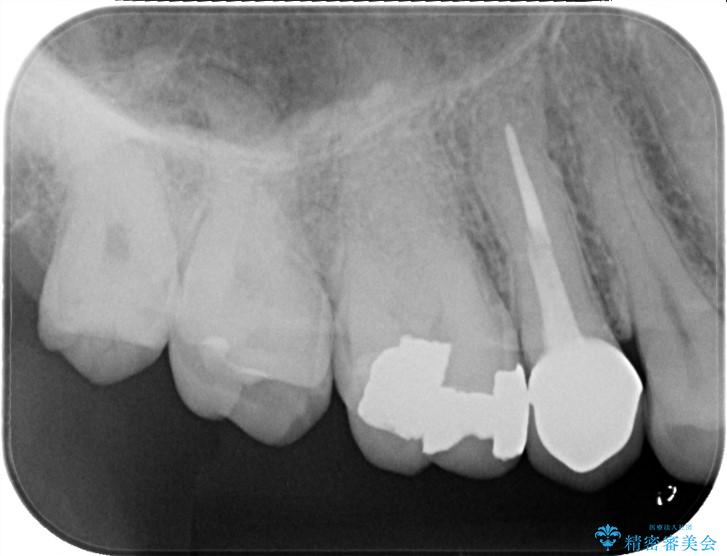

検査の結果、銀歯の下の歯質が薄くなっており、このままだと割れてしまう(破折)リスクが高い状態でした。

まず、古い銀歯を丁寧に外し、内部に虫歯がないか確認しました。

その後、残りの歯を保護して強度を上げるため、適合性が高いオールセラミッククラウンの作成・装着を行いました。